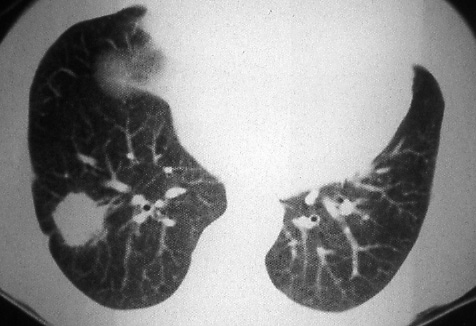

Fig. 38b: Computed tomographic scan (lung windows) through the lesion (Fig. 38a) demonstrates the cancer to better advantage and shows tags to the pleura.